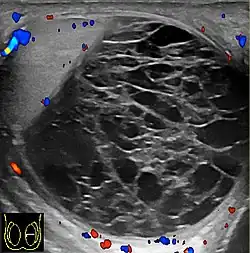

Hemoscrotum can follow trauma (such as a straddle injury) or can be a complication of surgery. It is often accompanied by testicular pain. It has been reported in patients with hemophilia and following catheterization of the femoral artery. If the diagnosis is not clinically evident, transillumination (with a penlight against the scrotum) will show a non-translucent fluid inside the scrotum. Ultrasound imaging may also be useful in confirming the diagnosis. In severe or non-resolving cases, surgical incision and drainage may be required. To prevent recurrence following surgical drainage, a drain may be left at the surgical site.

- Ultrasound

Current research is ongoing for proper diagnosis and helping to differentiate among other conditions. Doppler ultrasound in a retrospective study was shown to be helpful for differential diagnosis of patients with acute scrotum.[12] Accuracy of imaging studies is higher for the differential diagnosis of testicular torsion and epididmo-orchitis, which there can still be the possibility of misdiagnosis for hematoceles due to testicular torsion.[12] Further research in this area shows importance for surgical decision making in hematoceles.[12]